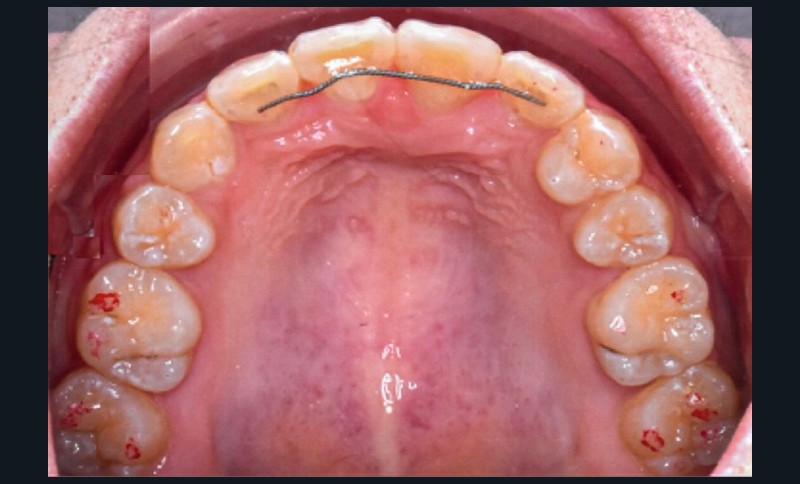

L’objectif du traitement est la correction de la DDA tout en assurant le remplacement de la 21 compromise. Décision a été prise d’extraire 34 et 44, ainsi que 21 et 14. La traction de la 23 a été réalisée à l’aide de forces légères, sur un arc transpalatin (fig. 9). Le nivellement et l’alignement, puis une mécanique par glissement ont permis d’aménager l’espace suffisant à la stratification de la canine. Elle associait un ressort en nickel-titane à des élastiques de Classe II (4 ½ oz, 3/16’’) sur un arc en acier .019×.025. Une phase d’ingression a été réalisée pour ajuster le niveau du bord libre de la canine à celui de l’incisive controlatérale (fig. 10-12).

Les corrections esthétique et fonctionnelle de la canine ont été effectuées par stratifications de résine composite (fig. 13). Au préalable, une simulation numérique de la nouvelle forme à donner à la canine a été élaborée. Une fois imprimée, cette simulation a servi à fabriquer une clé en silicone moulant les faces palatines des incisives. Cette clé a été garnie d’une fine couche composite de masse « émail » (Miris, ColteneR, Suisse) qui a été polymérisée une fois replacée en bouche pour constituer une coquille palatine. Afin d’élargir légèrement le profil d’émergence, des matrices (Slick Bands Margin Elevation, Garison, R USA) ont été insérées dans le sulcus des faces proximales avant d’y fouler une fine couche de composite. La coquille a ensuite été remplie de différentes masses de composite « dentine ». Une dernière fine couche de composite de masse « émail » a finalement été appliquée en surface avant de procéder au polissage et aux finitions. Après contrôle des axes, la fermeture réciproque des espaces d’extraction s’est poursuivie. Cette phase a été suivie par les finitions, puis la dépose. Des fils collés au maxillaire et à la mandibule assurent la contention, complétés par une gouttière thermoformée maxillaire (fig. 14-20).